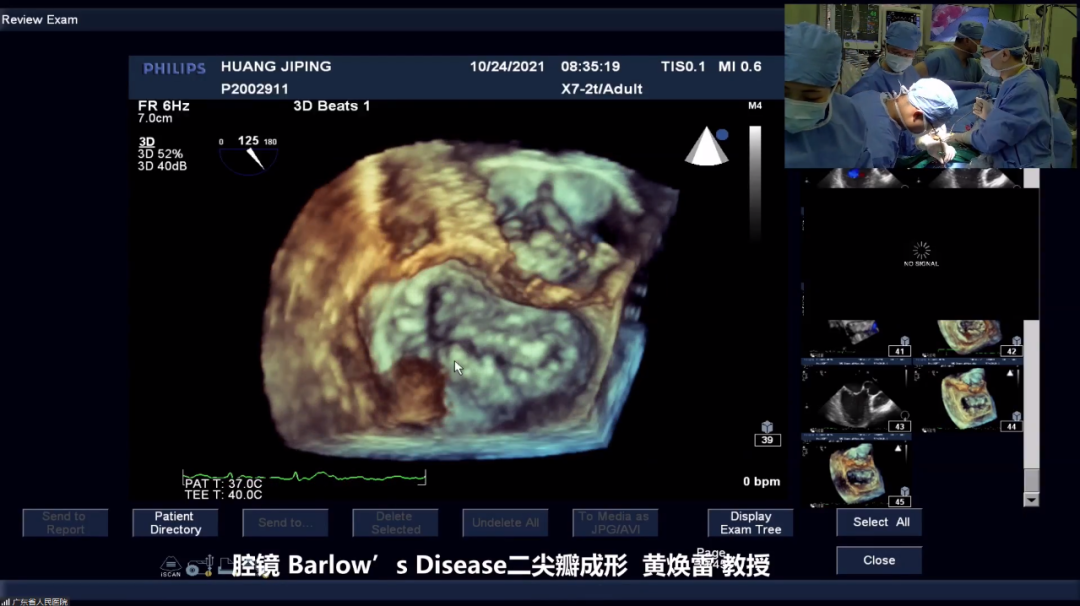

本场分论坛以广东省人民医院黄焕雷教授的腔镜Barlow’s Disease二尖瓣成形手术直播开始。

手术直播过程中,线下会场专家与主刀医生进行实时交流,探讨Barlow成形各种技术要点。最终二尖瓣修复取得圆满效果。